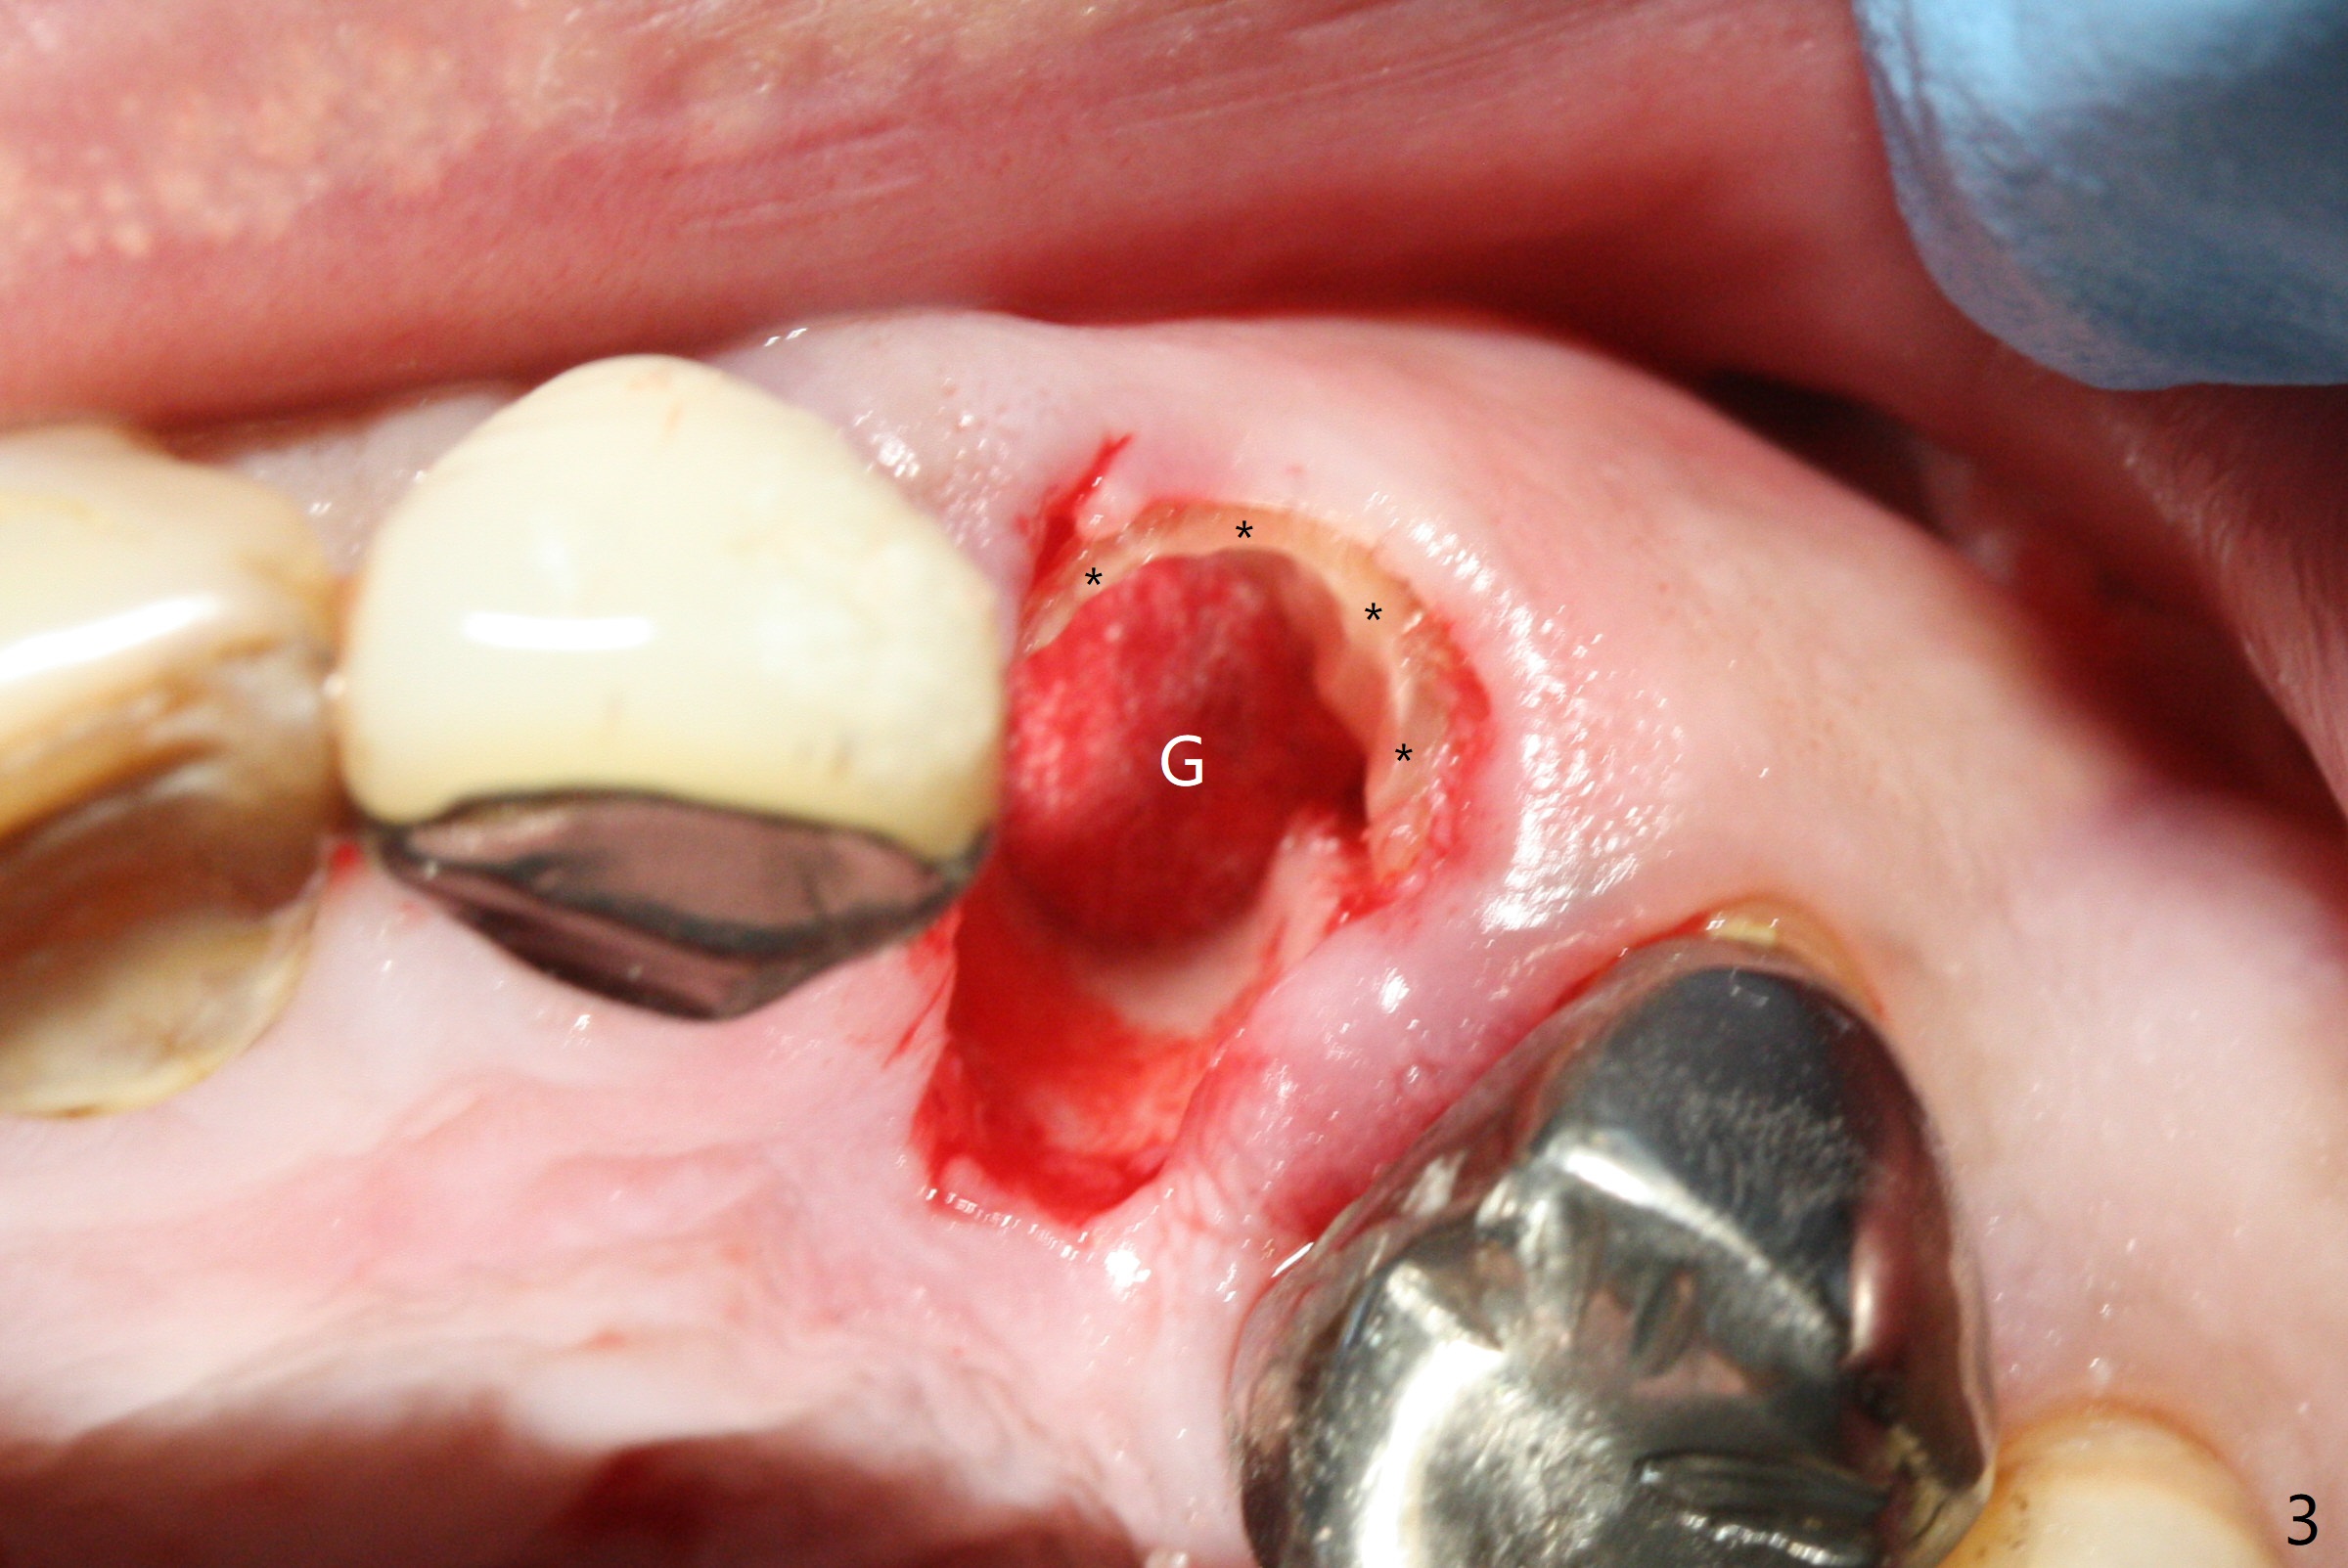

Extraction of the residual root at #11 (Fig.1) turns out to be difficult (Fig.2 (arrow: after use of small elevator). The tooth is sectioned (Fig.2 *); the palatal portion is removed, while the buccal one is trimmed until new moon-shaped and subgingival (Fig.3 * (gauze (G) packed in the socket while photo taking)). Initial osteotomy is 20 mm deep with nasal floor perforation (Fig.4). The subsequent depth is 17 mm (Fig.5). When a 5x17 mm tissue-level implant is placed (Fig.6,7; >60 Ncm), there is a gap between it and the socket shield (Fig.6 *). Gap-filling Vera Graft (Fig.8 *) also covers the shield prior to fabrication of an immediate provisional (Fig.9). There is no apparent bone loss 3.5 months postop (Fig.10). There is no buccal plate resorption 9 months postop (Fig.11). The implant is doing well 2 years postop (1 year 9 months post cementation, Fig.12).